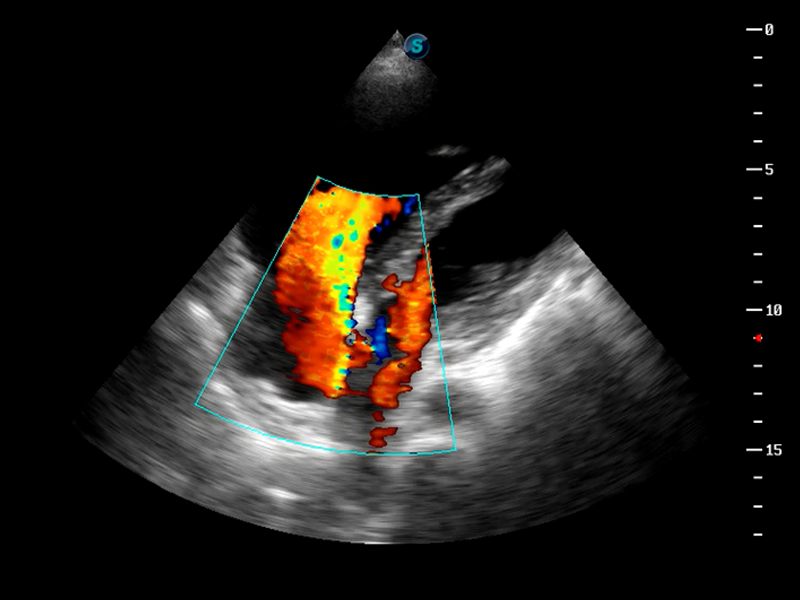

成像技术

AutoC智能血流追踪